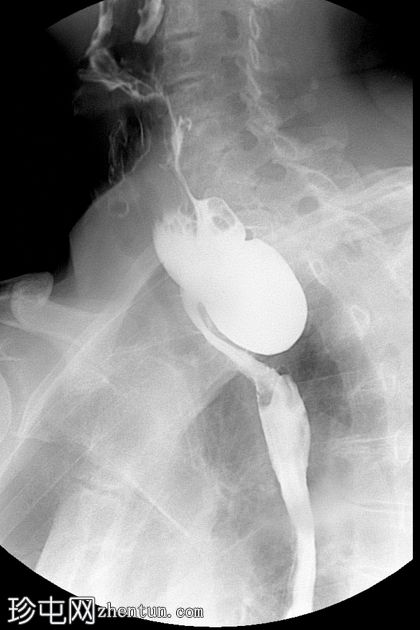

钡餐检查

2.jpeg

斜位

可见一充满造影剂的、向后突出的憩室,位于咽食管交界处后壁,大致在T1椎体水平。憩室颈部狭窄,与颈段食管相通。吞咽时憩室充满造影剂,延迟显像显示造影剂滞留。食管其余部分管径和走行正常。未见远端梗阻。

表现为后正中线向外突出的囊状物,颈部狭窄,位于 T1(C5-C6)水平或略低于该水平。

钡餐侧位片显示最佳。